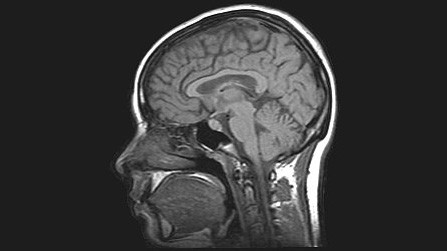

La herramienta AlzTools 3D Slicer utiliza rutinas espaciales para analizar las imágenes de resonancia magnética (IRMs), y ha sido desarrollada por los ingenieros informáticos de la empresa española Elecnor Deimos, basándose en la experiencia acumulada durante los años de desarrollo de software para la misión Envisat de la ESA.

“El análisis de las imágenes por satélite se puede comparar con lo que tienen que hacer los médicos para comprender el resultado de los escáneres cerebrales, como las IRMs”, explica Fernández de la Peña.

“Los médicos también tienen que identificar ciertas características en la imagen que pueden ser un indicativo de disfunciones cerebrales”.

Los científicos de Deimos utilizan AlzTools para analizar los datos tomados por un escáner cerebral, en vez de un satélite de observación de la Tierra. En lugar de una cosecha o de una carretera, analizan zonas del cerebro como el hipocampo, cuya atrofia está relacionada con el Alzheimer.